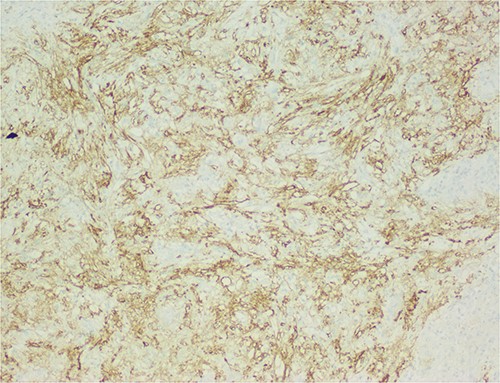

The histological evaluation of the surgical specimen revealed a storiform fusiform cell neoplasm with expansive borders, areas of a myopericytomatous pattern, and the presence of rhabdoid cells (Fig. 4). The neoplastic cells, spindled to oval, with eosinophilic and granular cytoplasm and with mild nuclear atypia, were organized in small bundles (Fig. 5). Anomalous arterial structures were observed. Neither necrosis nor mitotic figures were identified. The immunohistochemical study revealed immunoreactivity of neoplastic cells for SMA, HHF35 (Fig. 6) and HMB45 (Fig. 7), Calponin, S100 and CD31. The margins did not intersect the neoplasm. Thus, contrary to the preoperative diagnosis of hepatocellular carcinoma, the morphological aspects and the immunohistochemical profile favored the diagnosis of epithelioid angiomyolipoma.

The neoplastic cells are also positive for HMB45, demonstrating the typical myo-melanocytic differentiation.